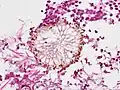

| Pulmonary invasive aspergillosis in a person with interstitial pneumonia (autopsy material), using Grocott's methenamine silver stain | |

On microscopy, Aspergillus species are reliably demonstrated by silver stains, e.g., Gridley stain or Gomori methenamine-silver.[27] These give the fungal walls a gray-black colour. The hyphae of Aspergillus species range in diameter from 2.5 to 4.5 μm. They have septate hyphae,[28] but these are not always apparent, and in such cases they may be mistaken for Zygomycota.[27] Aspergillus hyphae tend to have dichotomous branching that is progressive and primarily at acute angles of around 45°.[27]

Aspergillus vesicle (HE stain)

Aspergillus vesicle (HE stain)